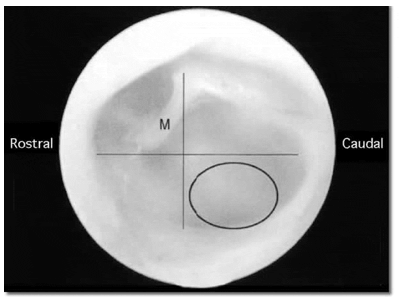

La otoscopía, que puede requerir anestesia general, permite visualizar las características de la membrana timpánica, que estará alterada en afecciones del oído medio/interno. En la misma maniobra se puede realizar una miringotomía (aspiración por abordaje ventrocaudal de la membrana timpánica), que permite la recolección de líquido de la cavidad timpánica para su posterior análisis (citología, cultivo y antibiograma) (Figura 9).

Figura 9: Membrana timpánica izquierda de un gato normal. Nótese el área en el cuadrante caudoventral (círculo), sitio recomendado para la miringotomía, a los efectos de evitar el daño de los huesecillos auditivos (M: mango del martillo) y las ventanas redonda y oval del oído medio (tomado de Le Couteur RA, Vernau KM. Enfermedades vestibulares del gato. Selecciones Veterinarias. Vol.8, No.6,596-613, 2000).